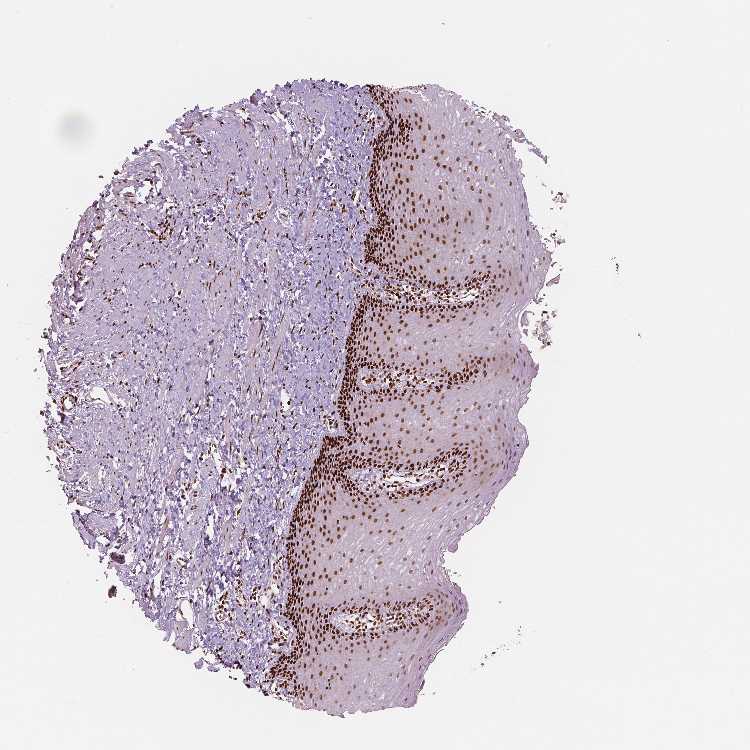

ESOPHAGUS - Antibody stainingi

Antibody staining in the annotated cell types in the current human tissue is reported as not detected, low, medium, or high, based on conventional immunohistochemistry profiling in selected tissues. This score is based on the combination of the staining intensity and fraction of stained cells.

Each image is clickable and will lead to virtual microscopy that enables deeper exploration of all samples and also displays staining intensity scores, fraction scores and subcellular localization as well as patient and tissue information for each sample.

Antibody HPA015055Antibody HPA061646Antibody CAB068177Antibody CAB068178

Squamous epithelial cells MediumHighMediumHigh